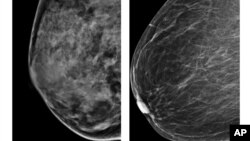

زنانی که بافت پستان آنها متراکم تر است، خطر ابتلا به سرطان پستان در آنها بیشتر است. تصویر سمت چپ، پستان متراکمتر را نشان می دهد.

"انجمن سرطان آمریکا" با صدور توصیه جدیدی می گوید بیشتر زنان باید آزمایش های سالانه غربالگری سرطان سینه را به جای ۴۰ سالگی، از ۴۵ سالگی آغاز کنند. این نوع آزمایش ها کمک می کند که افراد، و در این مورد زنان، ابتلای احتمالی به سرطان را زودتر متوجه شوند و درمان آن را زودتر آغاز کنند.

"انجمن سرطان آمریکا" همچنین اکنون توصیه می کند که زنان از ۵۵ سالگی، آزمایش های غربالگری سرطان پستان را هر دو سال یک بار انجام دهند.